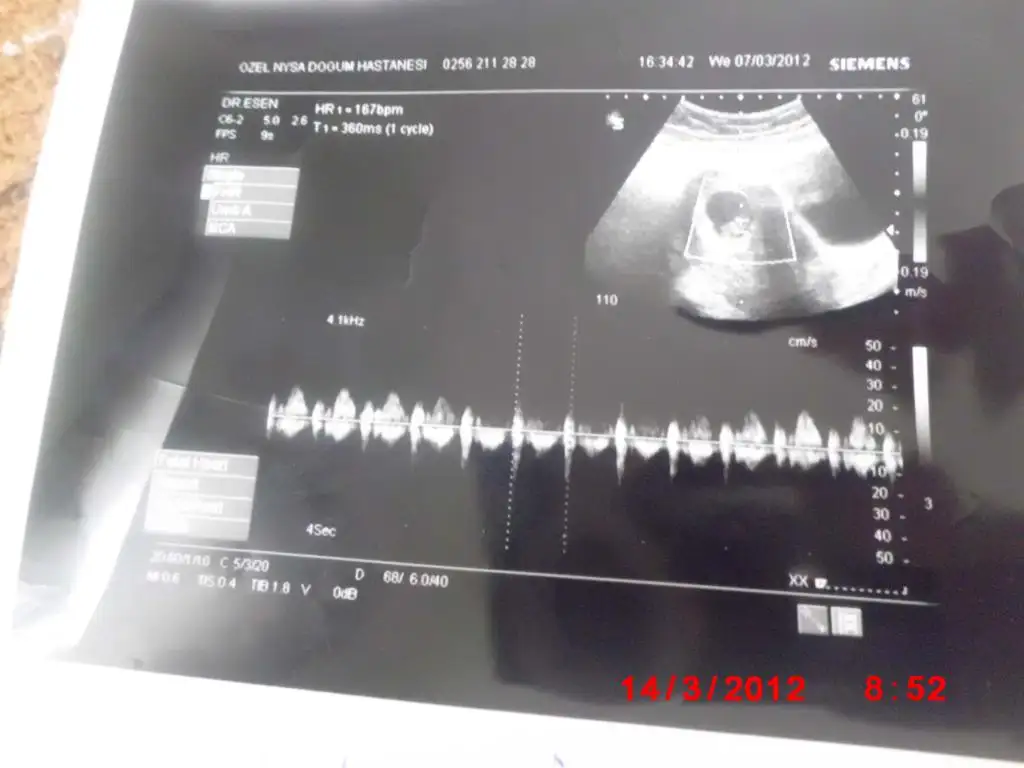

bugün sizlere bebişimin 8 haftalık ultrason resmini paylaşmak istedim

Eki Görüntüle 367104

Eki Görüntüle 367105

Eki Görüntüle 367103